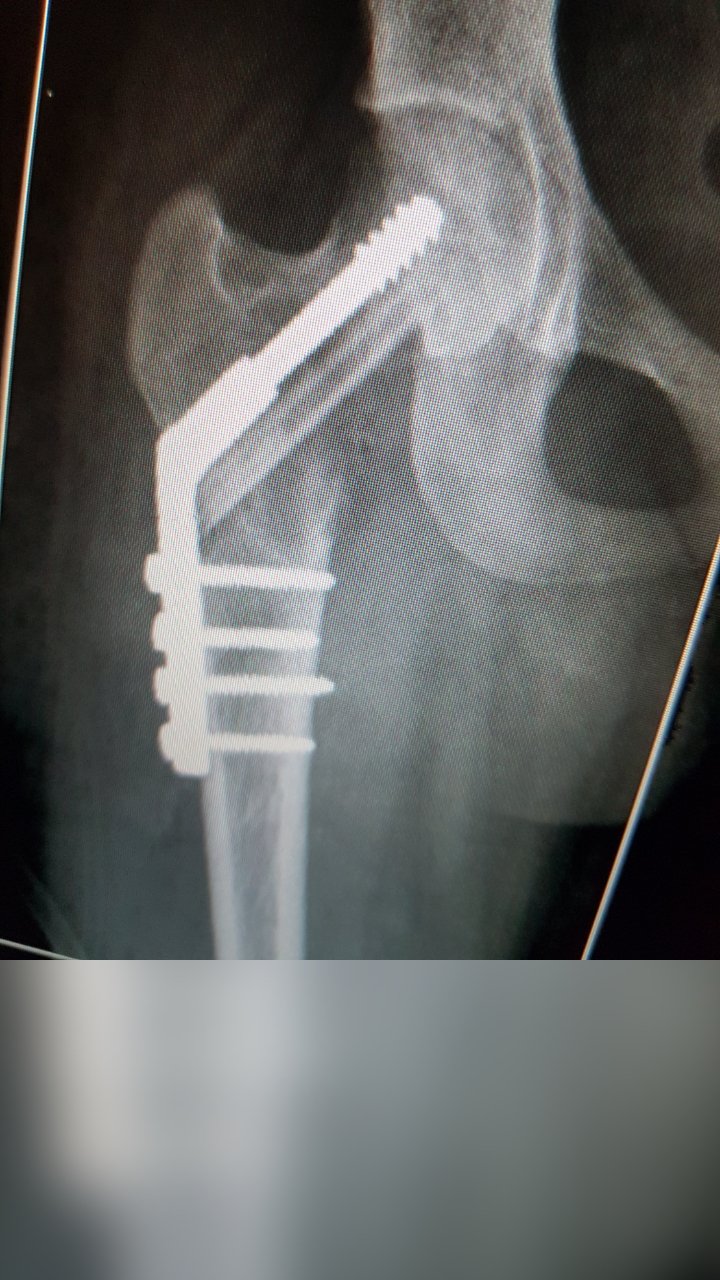

ANEURYSMAL BONE CYST NECK OF FEMUR SURGERY